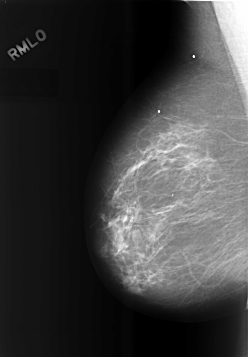

C_0483_1.RIGHT_MLO

RIGHT_CC LINES 5712 PIXELS_PER_LINE 4080 BITS_PER_PIXEL 12 RESOLUTION 50 NON_OVERLAY

RIGHT_MLO LINES 5712 PIXELS_PER_LINE 3976 BITS_PER_PIXEL 12 RESOLUTION 50 NON_OVERLAY